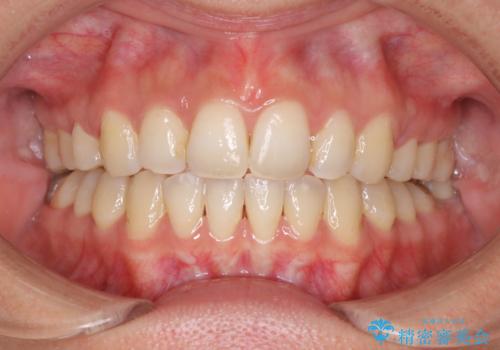

前歯がしっかり下がることで、上下の前歯があわさり食事もしやすくなったと言っていただきました。

- 出っ歯で口が閉じずらくて、前歯でものかが噛み切れないとのことで来院されました。

上顎の前歯が前方に傾斜して、下顎の前歯と接触していない状態でした。